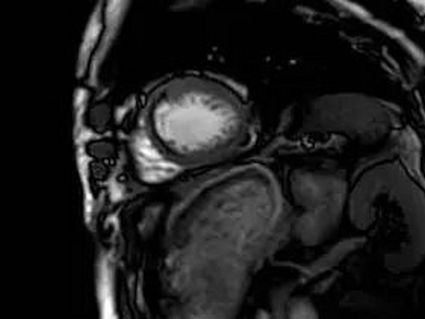

1.借助心脏电影,完成心功能分析。

5.心肌致密化不全。